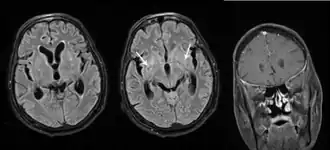

- Hidrocefalia, con los signos y síntomas correspondientes a esta.

Diagnóstico

Se realiza con:

- Detección de antígeno polisacárido de criptococo por aglutinación en látex.

- Demostración del organismo en preparados de tinta china en el LCR (positivo en un 50% de los casos).

- Cultivo de LCR (positivo en un 75% de los casos).